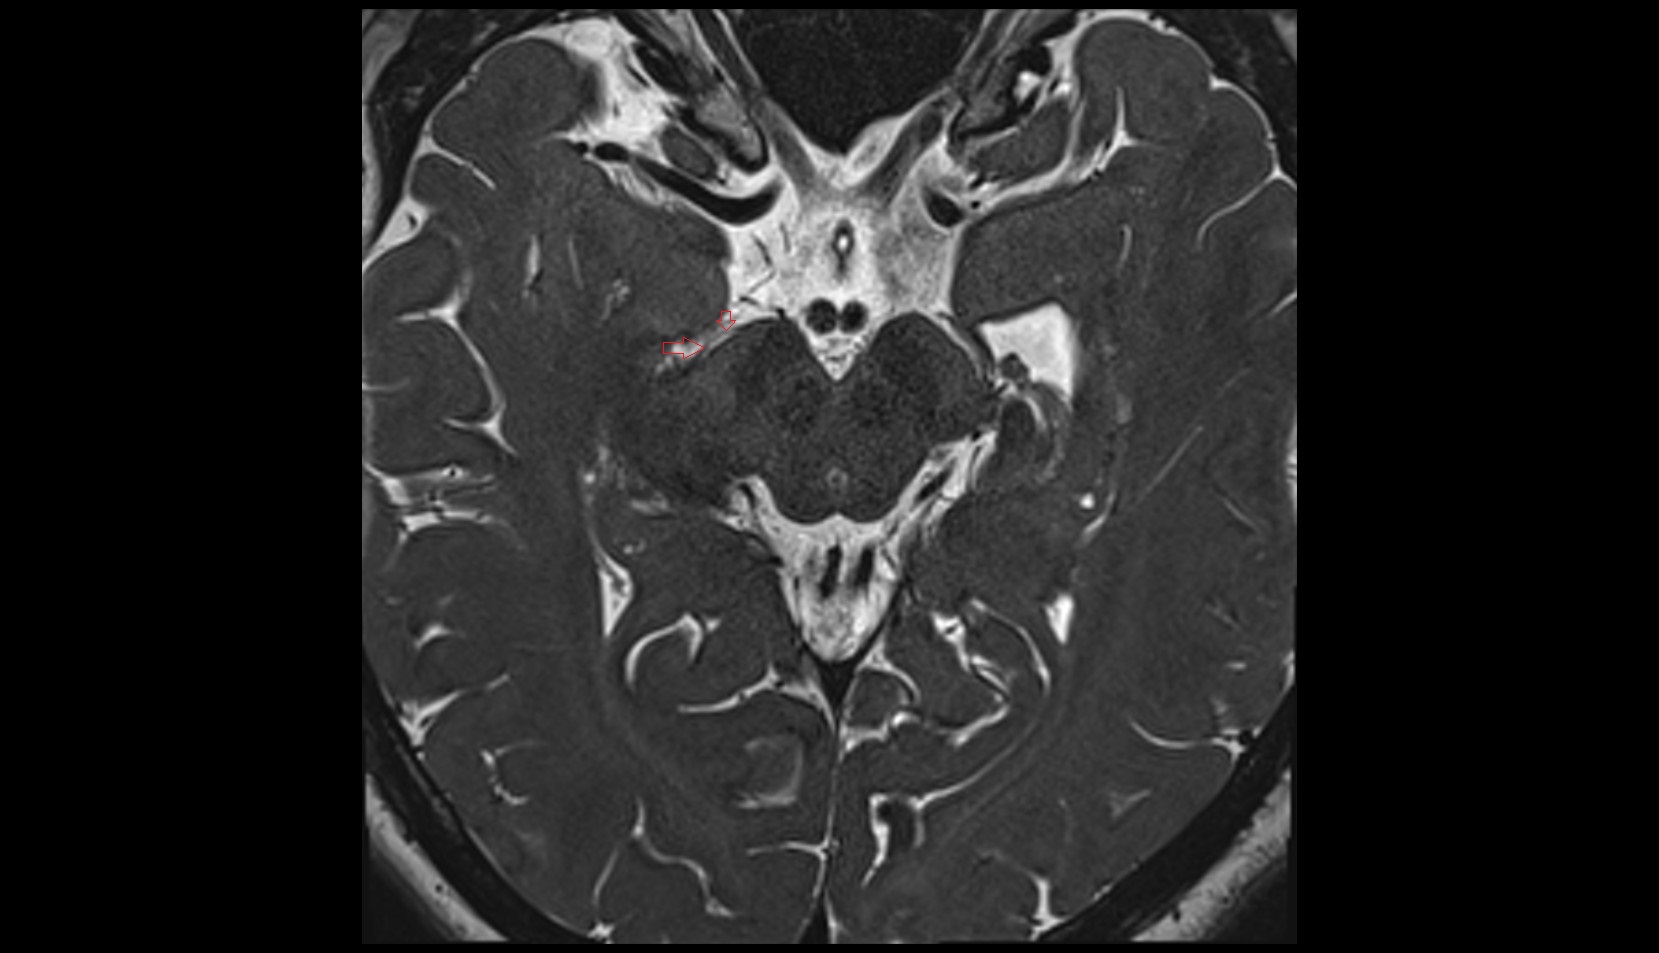

- Cerebellopontine angle

- Cerebellopontine cistern

- Pontocerebellar cistern

- Lateral aperture of fourth ventricle (foramen of Luschka)